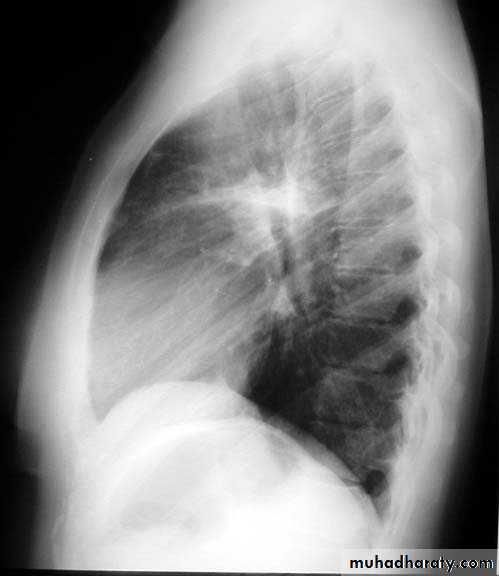

Lamellar pleural effusion